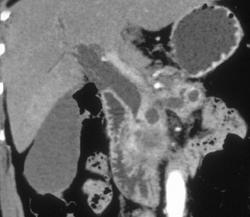

Chronic Pancreatitis